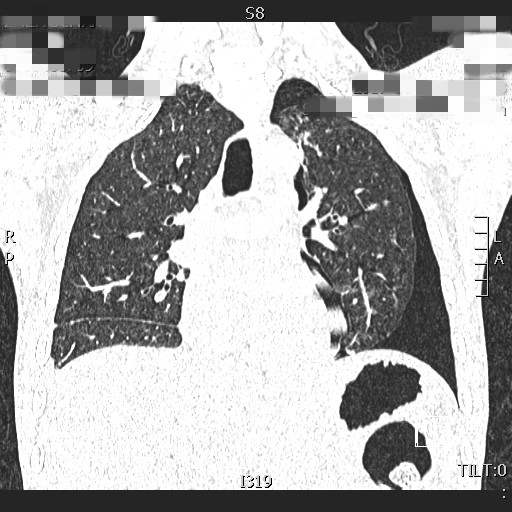

小马的肺部ct

完善胸部CT后,小马确诊为“自发性气胸”,气胸量较大,考虑可能为呼吸道病毒感染后发生肺部病变,剧烈运动诱发了自发性气胸。收住院进行治疗5天后复查胸片,气胸已基本吸收,小马转危为安。